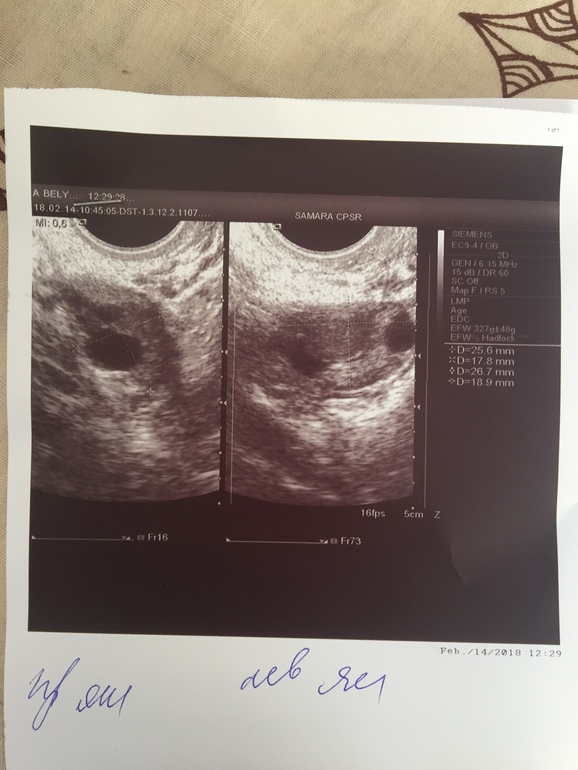

Эндометрий 17,4 на 16 дц

Приветик мои хорошие. Долго меня тут небыло. Решила отдохнуть полгодика и вот снова в бой... и в первый же день бах... вчера после отпуска... была у репродуктолога , брала направления в «Династию» в нашей больнице. Была на приеме у Столбовой М.Е, когда от неё уходила, она сказала, что ждёт меня с нестерпением на следующий приём, так как от меня у неё «каша» в голове... да, да - это ее слова. Мой АМГ был в августе 0,44... в декабре 0,77 при этом созревание фолликул у меня норм... я ее спросила может ИИ пробовать... на что она мне ответила, что на моем бы месте она бы огромными шагами шла к ЭКО!!!! И добавила, что бесплатно с таким АМГ мне откажут и только с донорской яйцеклеткой(((( я про это слышала, но пока конечно не готова к донорской яйциклеткой, слышала, что и с таким амг сами беременеют. Вчера был 16 дц мы вот вот только прилетели с отпуска и я сразу побежала к репродуктологу.я попросила сделать УЗИ, Посмотреть овуляцию... и тут я ни как не ожидала такого результата. Легла, узистка начала смотреть и сразу говорит, ты вроде беременна!!!! Мои слова, я конечно буду очень рада, но наверно это невозможно... я тут по-поводу бесплодия... она говорит у тебя эндометрий островат, это возможность беременности, купи сегодня дорогой тест и сделай!!! На что я ответила, что сомневаюсь, что на 16 дц тест что то покажет. Про себя думаю, блин может смена климата, отдых и правда что то изменил.... ну тут мои мысли отпали, так как она начала говорить, что скорее всего овуляции небыло... в левом яичнике лоцируется пониженной эхогенности округлое образование тонкой капсулой диаметром 11,5 мм. Эндомерий толщиной аж 17,4 мм!!!!!!!! Заключение: эхо-признаки гиперплазии эндометрий. Эндометриома левого яичника. Я следом пошла обратно к врачу, показала ей УЗИ, она меня ждала.... говорит, что беременности не будем исключать, но эндометрий на 16 дц очень большой, обозначила что фолликул много - это хорошо при моем АМГ! Дала мне листок с кучей анализов для подачи документов на ЭКО, сказала, вдруг возьмут бесплатно! Мужу сдать анализы! Если будет задержка то сдать анализ на ХГЧ, а если придут М то на 6 дц приехать на УЗИ. Девулечки мои хорошие, кто... что... мне может сказать по моей всей ситуации??? Фото УЗИ ниже